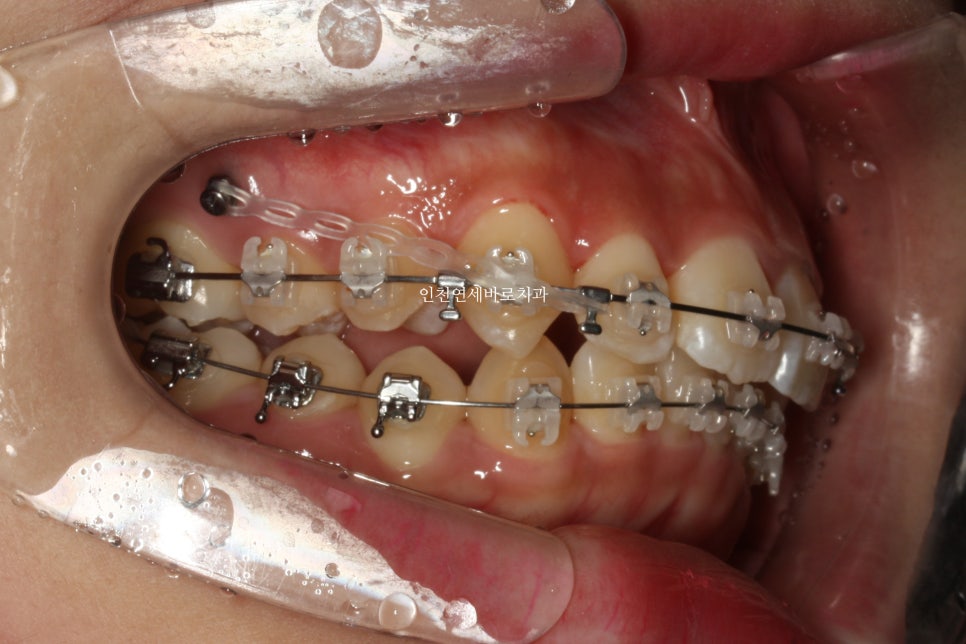

미니스크류를 총 6개 식립했던 환자분입니다.

골격에 대한 분석 후 위쪽 치열은 후방 + 상방 으로 당겼습니다.

치료가 마무리 되던 날 찍은 사진입니다.

미니스크류 = 나사는 유지목적으로 1년정도 유지하다가 제거했습니다.

교정이 약 2년 2개월만에 마무리가 되었습니다.